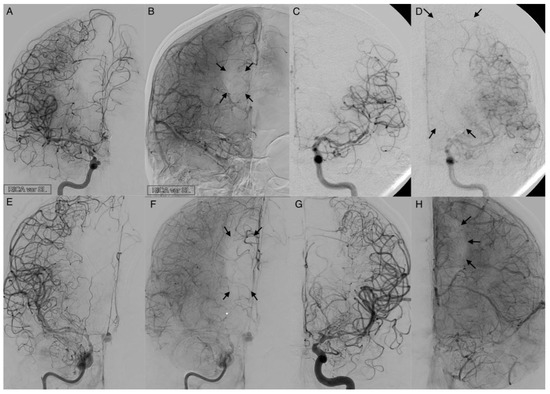

Figure 5. Activated leptomeningeal collaterals in anterior cerebral artery vasospasm. The angiograms show the extent of collateralization in four cases of severe cerebral vasospasm following aneurysmal subarachnoid hemorrhage. The arterial phase (A,C,E,G) reveals a strongly narrowed and decelerated anterior cerebral artery. In the parenchymal phase (B,D,F,H), activated leptomeningeal collaterals of the middle cerebral artery took over the retrograde supply of the decelerated parenchyma with varying extent of the remaining perfusion defect (arrows).